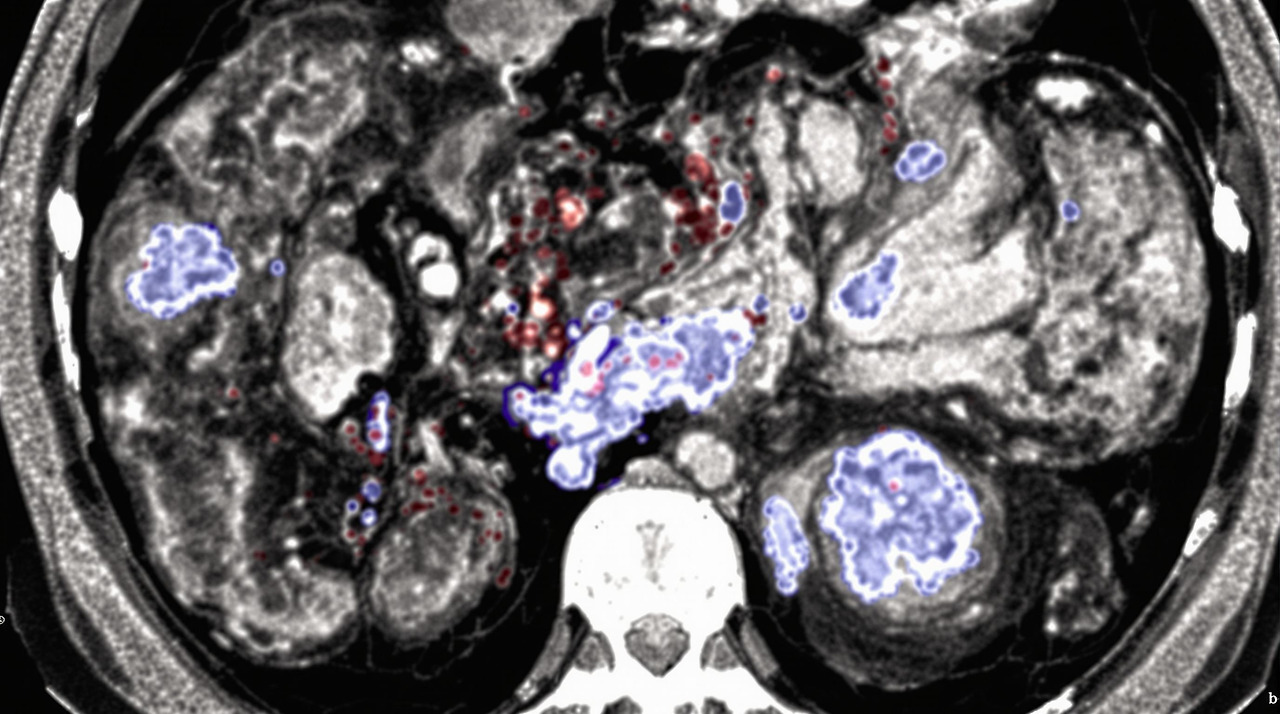

영상 검사는 대장 게실염 진단의 핵심입니다:

- CT 스캔: 게실염 진단의 가장 정확한 방법으로, 게실의 위치와 개수, 염증 정도, 합병증 여부를 확인할 수 있습니다. 조영제를 사용한 CT 검사는 정확도가 약 98%에 달합니다.

- 초음파 검사: 비침습적이며 방사선 노출이 없어 임산부나 젊은 환자에게 유용합니다. 그러나 CT에 비해 정확도가 낮고 검사자의 숙련도에 따라 결과가 달라질 수 있습니다.

- MRI: CT에 비해 비용이 높지만, 방사선 노출 없이 상세한 영상을 제공합니다. 특히 누공이나 복잡한 합병증 평가에 유용합니다.

- 대장 내시경: 급성기에는 천공 위험이 있어 피하는 것이 좋으며, 주로 염증이 완화된 후 게실의 상태를 확인하거나 다른 질환(대장암 등)과의 감별을 위해 시행합니다.